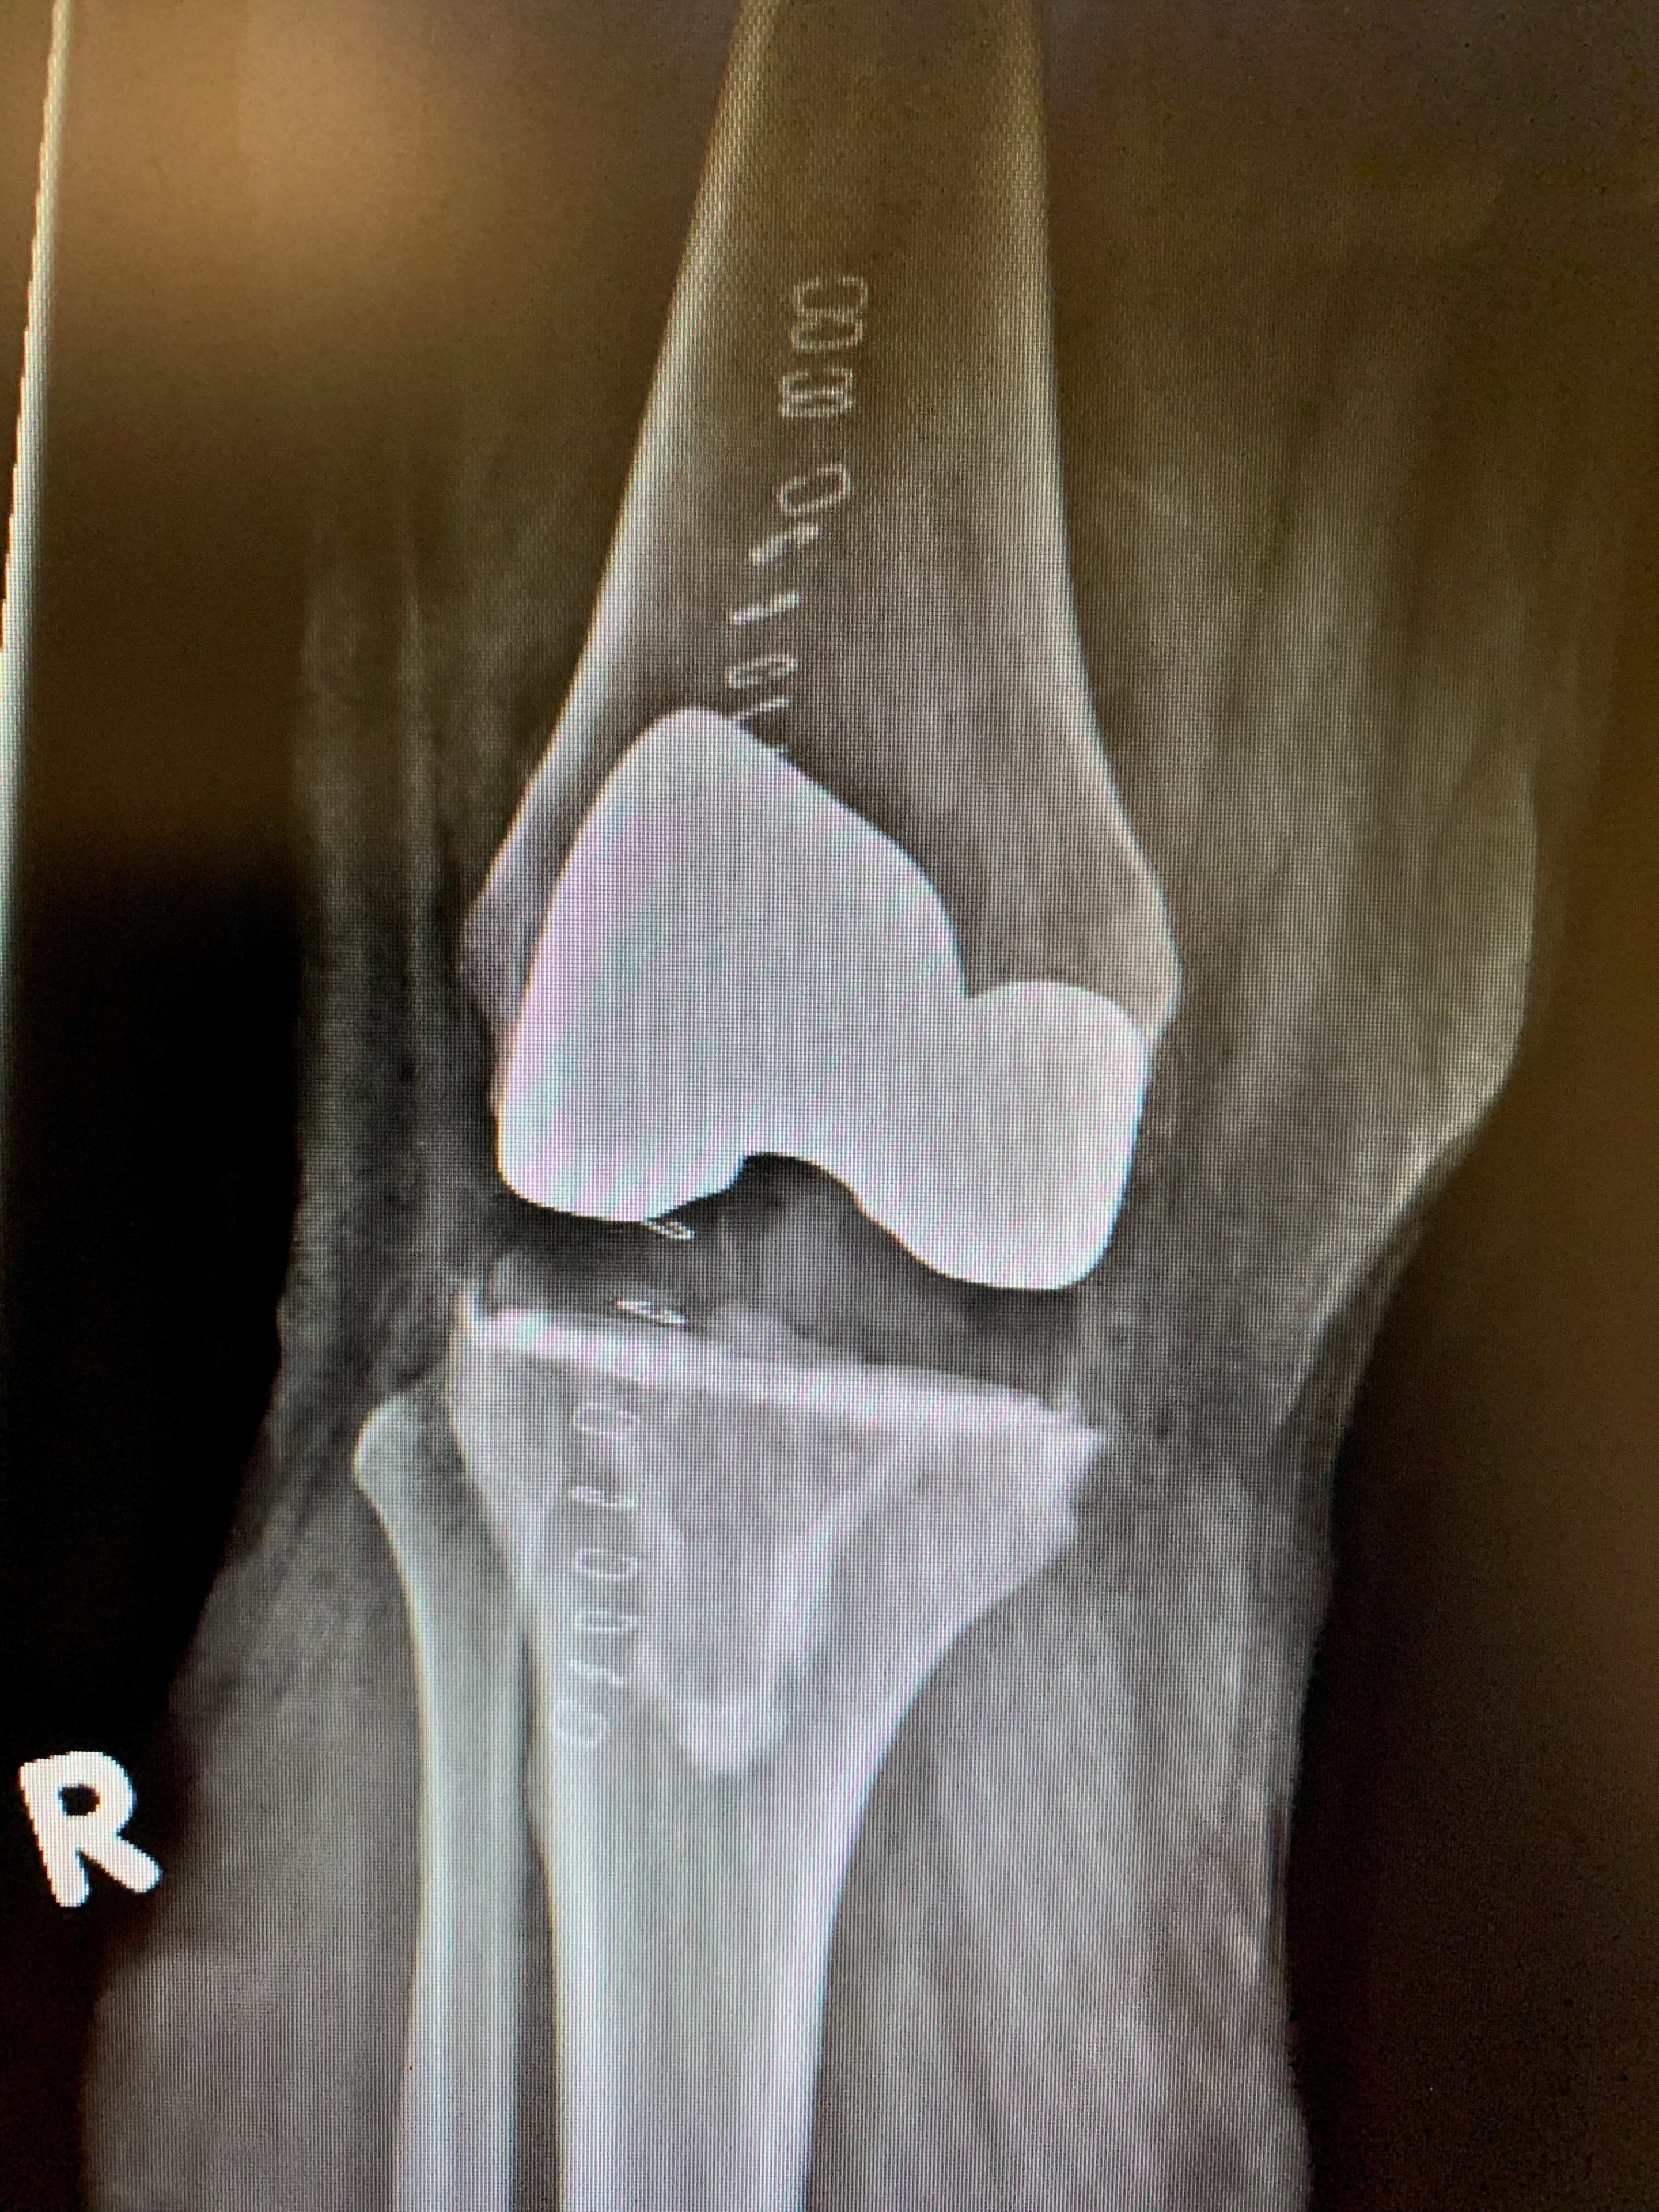

Finalmente lo consideramos candidato para la cirugía de artroplastia de rodilla y también pudimos ofrecerle una cirugía de instrumentación de rodilla específica para cada paciente. Esto implicó enviar al Sr. TF a una resonancia magnética de rodilla que de otro modo no habría recibido si estuviera recibiendo una cirugía estándar de instrumentación de rodilla. Esta exploración se envió luego a la empresa de implantes, que la utilizó para crear instrumentos específicos para la anatomía de rodilla del Sr. TF.

Estos instrumentos personalizados nos permitieron realizar cortes óseos específicos que coincidían con la superficie interna de la prótesis de rodilla. La ventaja de estos cortes es que resultan en la extracción mínima de hueso para completar el procedimiento. Los pasos del procedimiento en sí no cambian, y los componentes implantados coinciden con la geometría de la superficie externa de los implantes estándar para replicar una biomecánica optimizada.

El Sr. TF se recuperó muy bien de su procedimiento y fue dado de alta del hospital al día siguiente de la operación. Está bien un año después de la cirugía, y está satisfecho de haber tenido la oportunidad de beneficiarse de instrumentación específica para su anatomía, y la recomendaría a cualquiera que tenga una oportunidad similar.

Postoperatorio